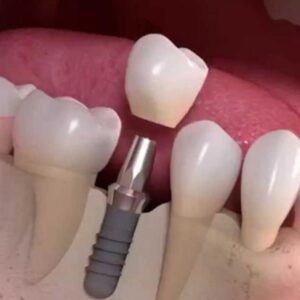

Impianti

L’implantologia dentale è una tecnica ampiamente diffusa che consente di sostituire i denti mancanti grazie all’uso di impianti studiati su misura per il paziente. L’impianto dentale deve integrarsi perfettamente all’osso mascellare o mandibolare e per questa ragione deve essere costruito con materiali biocompatibili. L’impianto dentale è un dispositivo medico necessario quando un dente naturale risulta...

In caso di denti mancanti una possibile soluzione è l’implantologia dentale. Questa tecnica consiste nell’inserire delle radici artificiali in titanio direttamente nell’osso mascellare o mandibolare. Sulle radici artificiali verranno poi applicate le protesi fisse. Nel caso in cui non ci fosse osso sufficiente non è possibile inserire gli impianti dentali. Molti pazienti che ricorrono all’implantologia soffrono di...